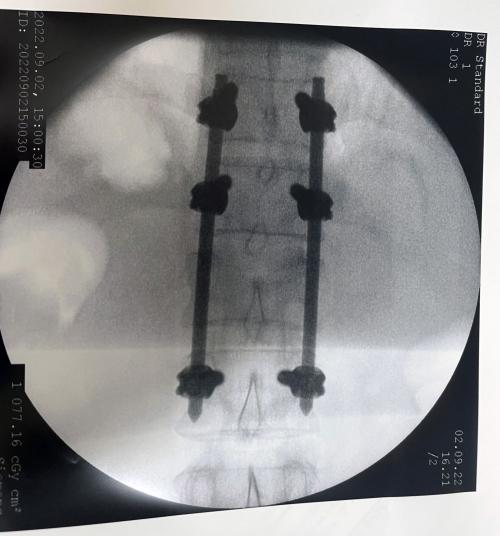

Tylko w ostatnich tygodniach ze złamaniem kręgosłupa zoperowano kilkunastu pacjentów. Operacje były wykonywane nowoczesną, małoinwazyjną metodą przezskórną.

Ta technika pozwala na szybki powrót chorego do sprawności. Już następnego dnia po zabiegu pacjenci stawali na własne nogi, a po kilku dniach samodzielnie opuszczali szpital. Wszystkie operacje odbyły się bez powikłań.